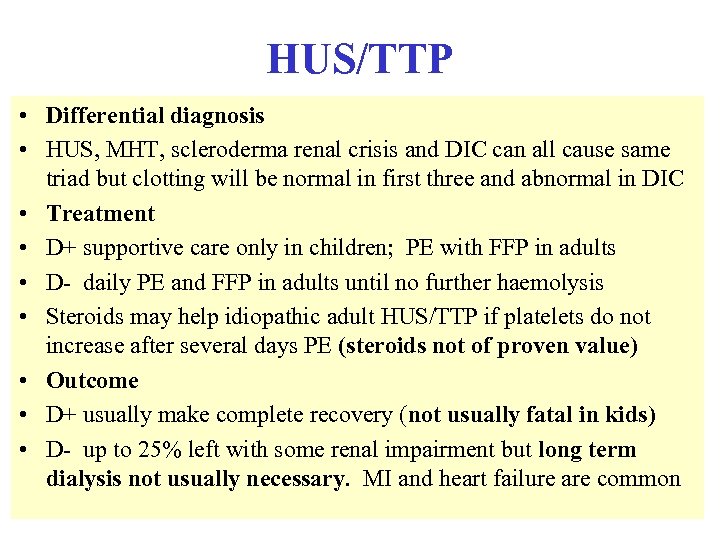

HUS/TTP • Differential diagnosis • HUS, MHT, scleroderma renal crisis and DIC can all cause same triad but clotting will be normal in first three and abnormal in DIC • Treatment • D+ supportive care only in children; PE with FFP in adults • D- daily PE and FFP in adults until no further haemolysis • Steroids may help idiopathic adult HUS/TTP if platelets do not increase after several days PE (steroids not of proven value) • Outcome • D+ usually make complete recovery (not usually fatal in kids) • D- up to 25% left with some renal impairment but long term dialysis not usually necessary. MI and heart failure are common

HUS/TTP • Differential diagnosis • HUS, MHT, scleroderma renal crisis and DIC can all cause same triad but clotting will be normal in first three and abnormal in DIC • Treatment • D+ supportive care only in children; PE with FFP in adults • D- daily PE and FFP in adults until no further haemolysis • Steroids may help idiopathic adult HUS/TTP if platelets do not increase after several days PE (steroids not of proven value) • Outcome • D+ usually make complete recovery (not usually fatal in kids) • D- up to 25% left with some renal impairment but long term dialysis not usually necessary. MI and heart failure are common